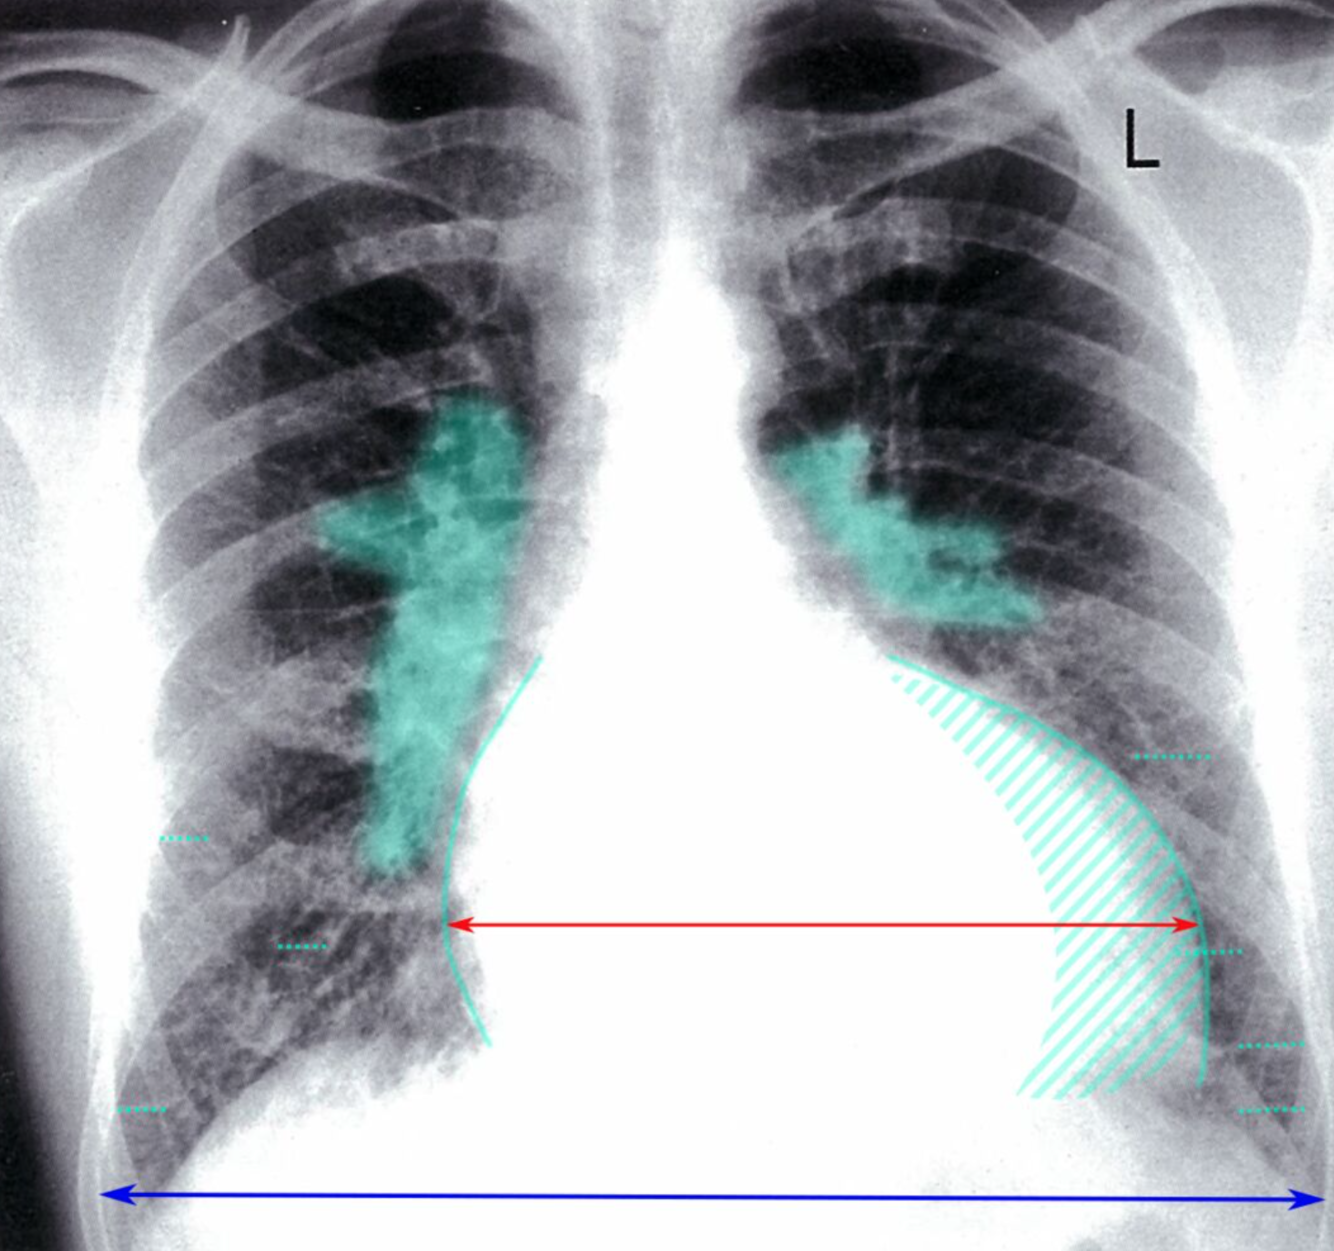

Cardiaque et pulmonaire

The cardiac silhouette is enlarged (hatched green overlay), with an increased cardiothoracic ratio > 0.50 (red line:blue line). Prominent central pulmonary vessels (green overlay) reflect vascular redistribution. Interlobular septal thickening (Kerley B lines) is seen in the lower zones (examples indicated by dotted green lines)